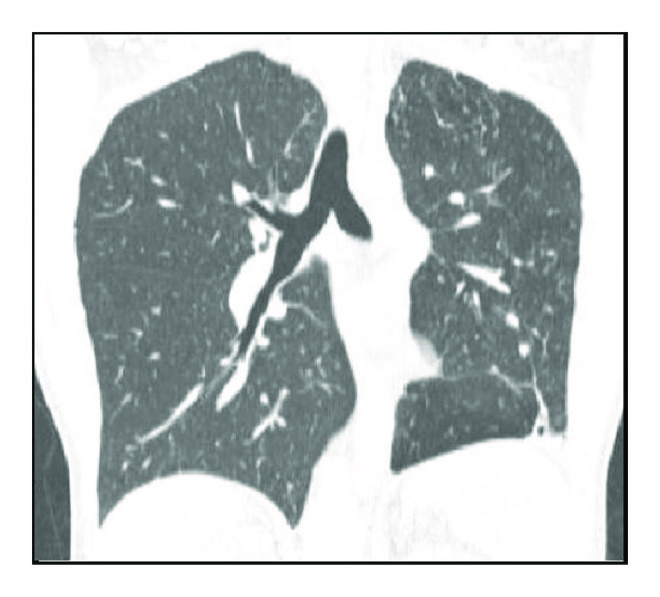

The analysis of CT2 followed the same methodology. There was an absolute predominance of airway changes characterized by cylindrical bronchiectasis, pulmonary parenchyma distortions, and 1–3 cm diameter nodules (Table 2 and Figure 2).

(a)

(b)

(c)

(d)

In CT2, we identified a high frequency of changes considered sequelae and diagnosed them as architectural distortion in 92% of cases and cylindrical bronchiectasis in 86% of cases. Thin-walled cavitary lesions and reduced injury volume have been reported in several studies as radiographic and tomographic criteria for successful treatment of TB [16–18]. We observed that cavitary lesions with wall thickness of <3 mm did not disappear. Of note, we found that 48% of cases had persistent nodules between 1 and 3 cm in diameter. These surprising but rarely reported data deserve to be recognized by doctors and underscore the need for interpreting image data within a known clinical context, avoiding diagnostic and therapeutic procedures sometimes unnecessary in patients already treated. Certainly, the large number of sequelae found, notably those associated with bronchiectasis and residual nodules known as tuberculomas, may be associated with the long duration of the disease and the late diagnoses.